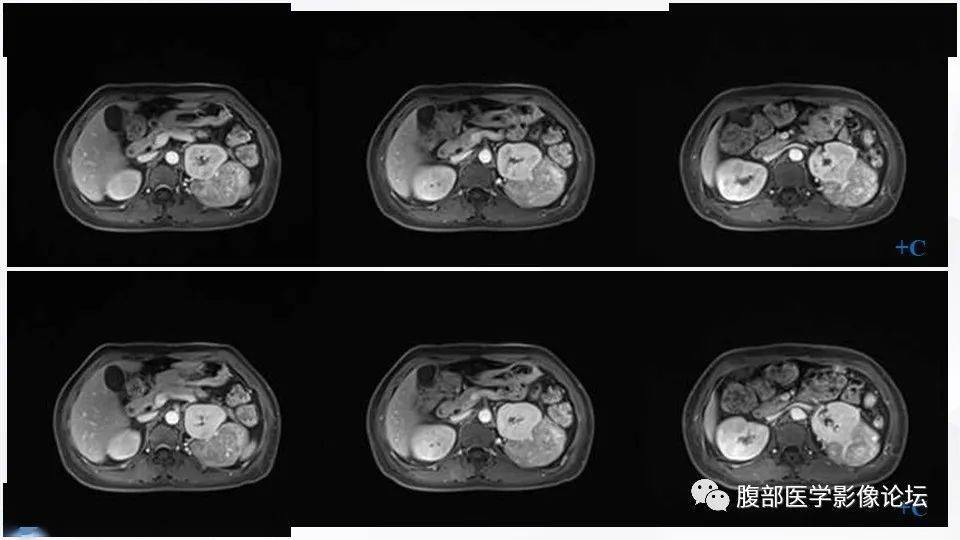

肾脏丨左肾eaml

图片尺寸960x540